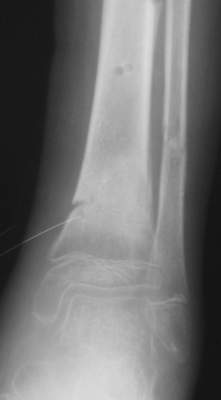

Нашел в комп-ре схожий случай:

1) з/репозиция, 2) фиксация 2 спицами, 3) аппарат, 4) фиксационные

спицы удалены...

См. аттачт.

А можно было наложить аппарат и по поводу ложного сустава...

По крайней мере не было бы укорочения (пусть и в 2 см)...

A> Это конечно дело жизненного опыта, но травматических пластичеких

A> деформаций у

A> подростков я не встречал.

Бывают.

Чаще - на уровне предплечья.

Например как "Монтеджиа-эквивалент".

Встречаются и при переломах голени (б/б с вальгусным смещением).

A> Тем более с такой дугой

A> и на этом

A> уровне.

К сожалению, в своем компьютере я таких случаев не нашел, но раза 2 встречал.